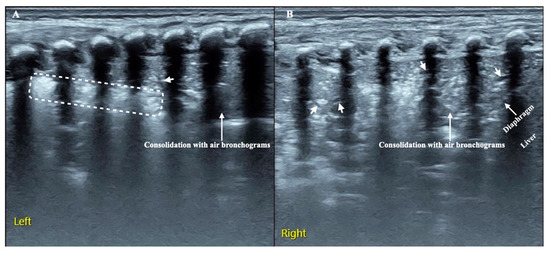

- Alamdaran, S.A.; Heidarzadeh, H.; Zavvar, N.; Badlee, Z.; Jaberi, M.; Ghasemi, A. Presentation of Sonographic Features of Pulmonary Invasive Fungal Disease in Six Children with Leukemia. Int. J. Pediatr. 2021, 9, 13203–13211. [Google Scholar] [CrossRef]

- Liu, J.; Ma, H.R.; Fu, W. Lung Ultrasound to Diagnose Pneumonia in Neonates with Fungal Infection. Diagnostics 2022, 12, 1776. [Google Scholar] [CrossRef]

| N. of Patients | Age | Microorganism | Consolidation | Atelectasis | Cavitation | Hyper– Echoic Nodule with Hypo– Echoic Rim | Hypo– Echoic Nodule with Hyper– Echoic Rim | Pleural Effusion | B–lines | |

|---|---|---|---|---|---|---|---|---|---|---|

| Children | ||||||||||

| Trinavarat 2012 [35] | 1 | 6 weeks | Aspergillus | 1 | 1 | |||||

| (100%) | (100%) | |||||||||

| Alamdara, 2021 [36] | 6 | 5-11 yrs | 1 Mucurmicosis, 5 Aspegillus | 5 | 2 | 2 | 4 | |||

| (83%) | (33%) | (33%) | (66%) | |||||||

| Liu J., 2022 [37] | 7 | Premature newborns | 5 C. albicans, 1 C. parapsilosis, 1 Aspergillus | 7 | 2 | 2 | 7 | |||

| (100%) | (33%) | (33%) | (100%) | |||||||

| Total | 14 | 13 | 2 | 3 | 2 | 4 | 2 (14%) | 7 | ||

| (93%) | (14%) | (21%) | (14%) | (28%) | (50%) | |||||